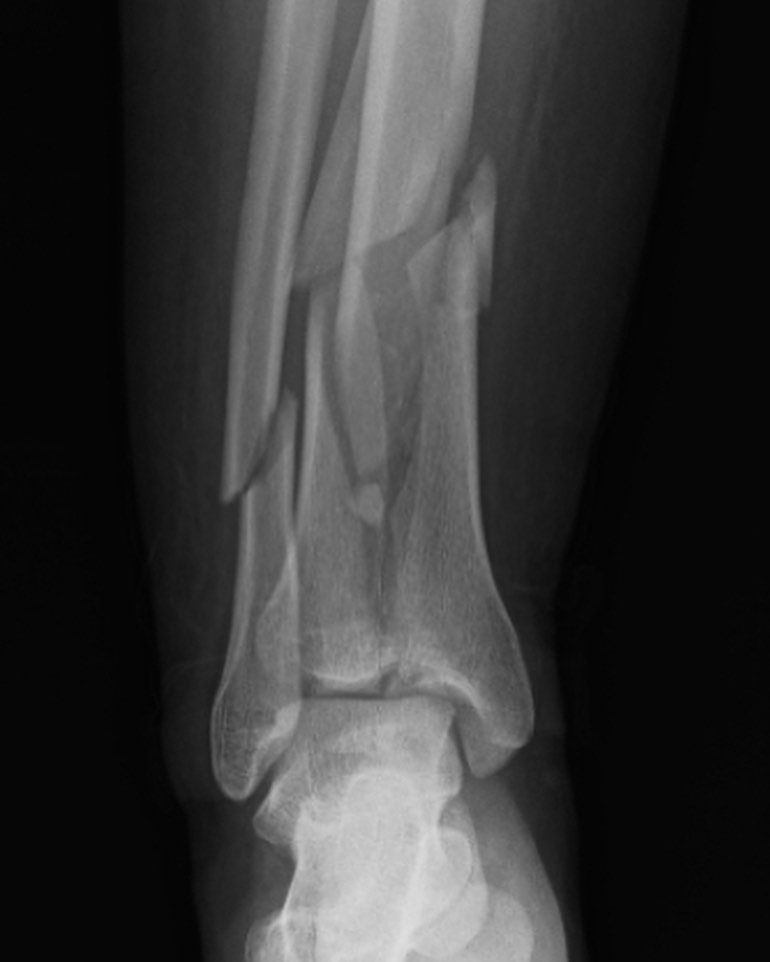

El manejo inicial de una fractura compleja de tibia representa un punto de inflexión en el proceso de recuperación del paciente. Tal como lo destacó el Dr. Escobar, la fijación externa emerge como una herramienta invaluable en esta etapa crítica.

La elección del tipo de fijador externo y el protocolo de tratamiento dependerán de diversos factores, como la localización y gravedad de la fractura, el estado de las partes blandas y las condiciones generales del paciente. Es fundamental que la decisión sea tomada de manera multidisciplinaria, involucrando al traumatólogo, el cirujano ortopédico y otros especialistas según sea necesario.